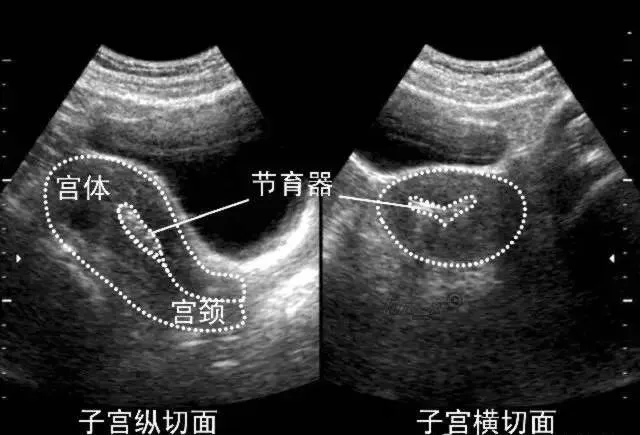

宫内节育器

●声像图表现:宫腔内线性、圆形或三角形强回声。

●宫内节育器位置正常:节育器强回声位于宫腔中心,其周围内膜显示为低回声的晕圈。在子宫纵切面可判断宫内节育器在宫腔内的位置正常位置的宫内节育器应全部位于宫腔内,且节育器最下缘不低于宫颈内口。